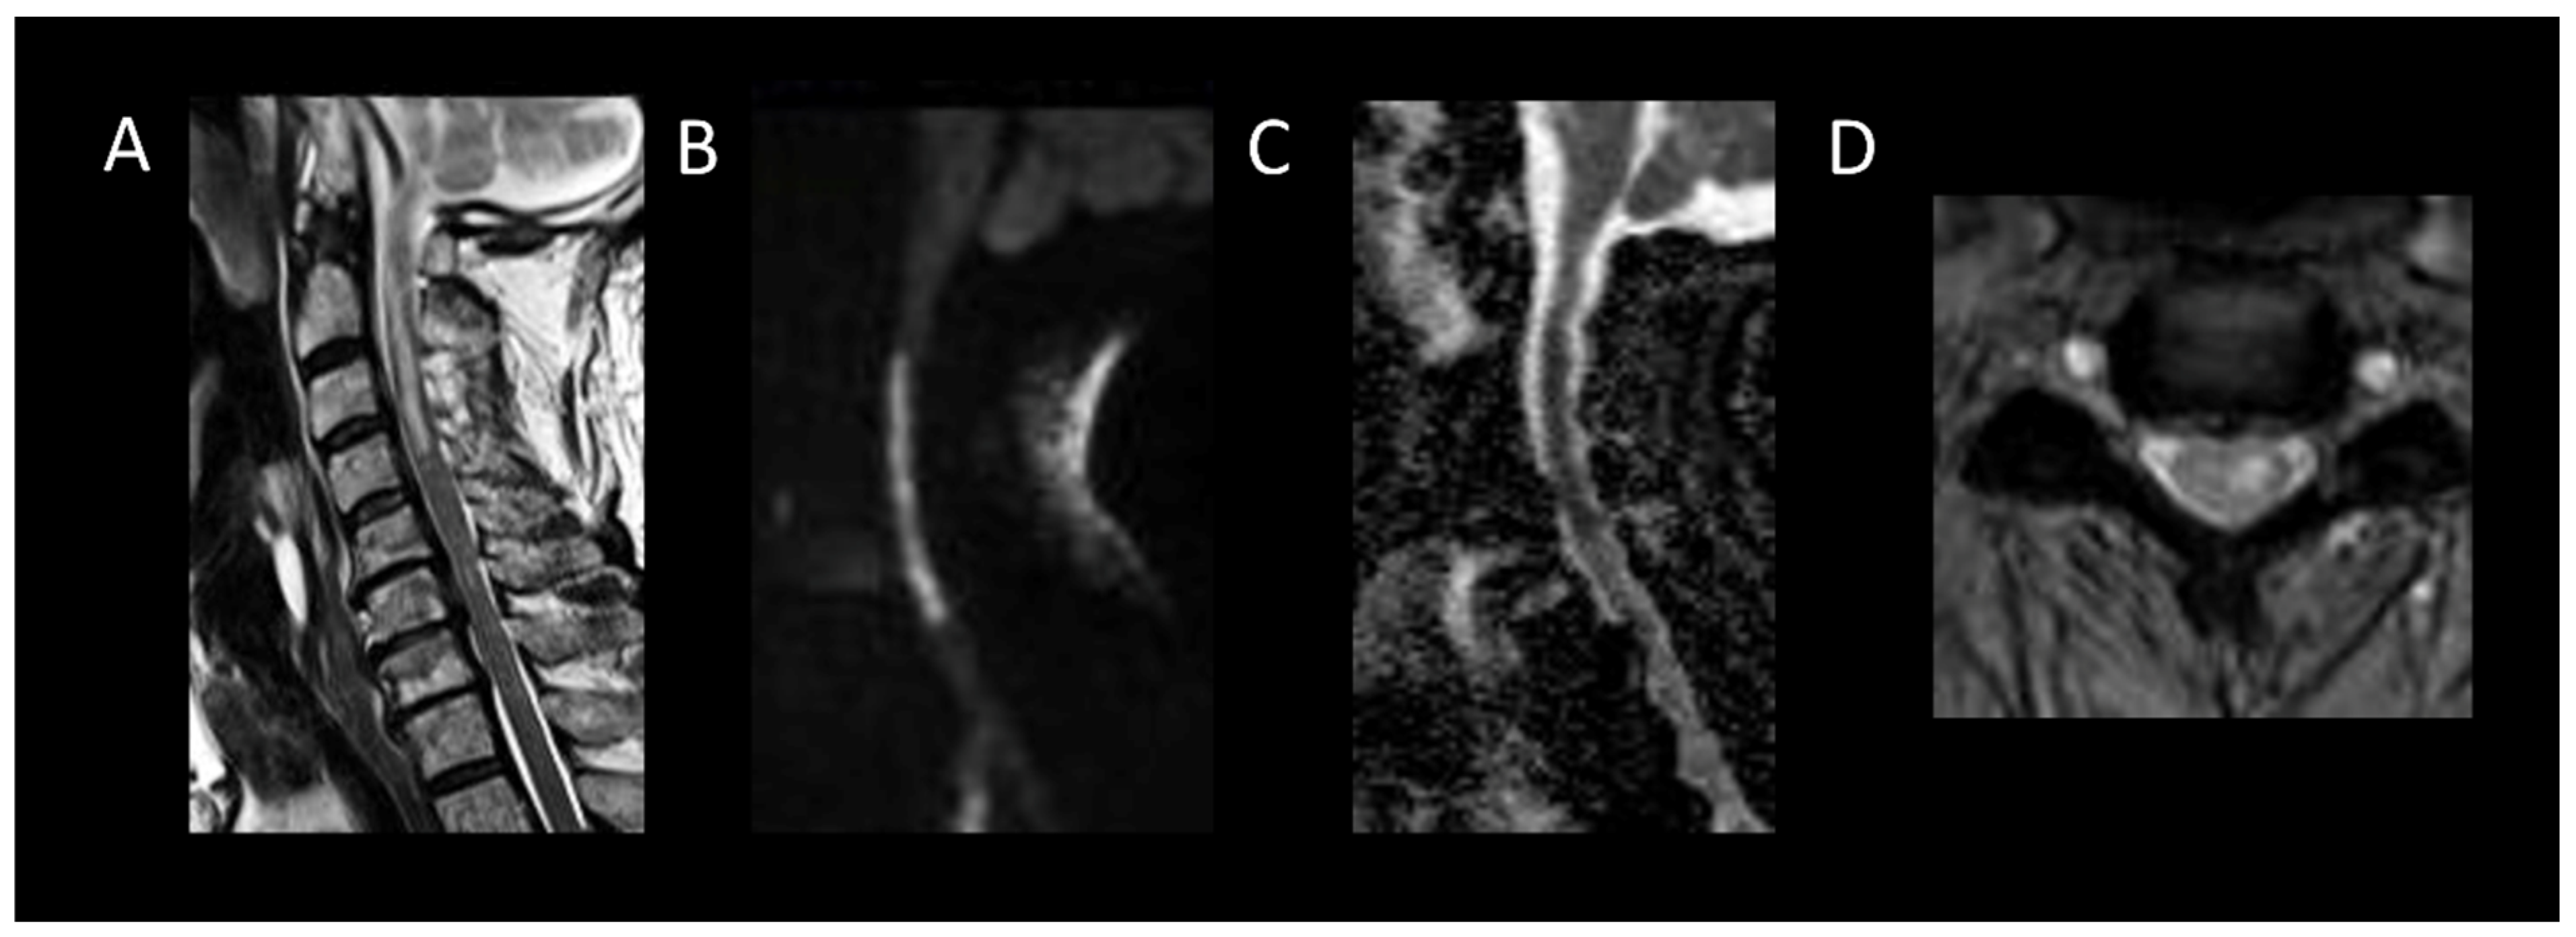

3.3.1. Spinal Cord Infarction